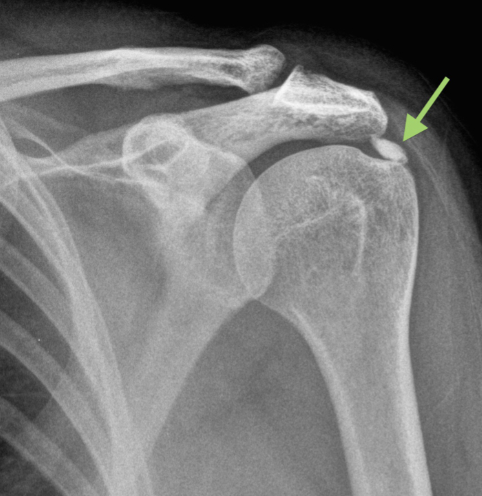

어깨 부위를 X-ray로 촬영하면 하얗게 석회화된 조직이 보입니다. 따라서 X-ray 검사만으로도 쉽게 진단할 수 있습니다.